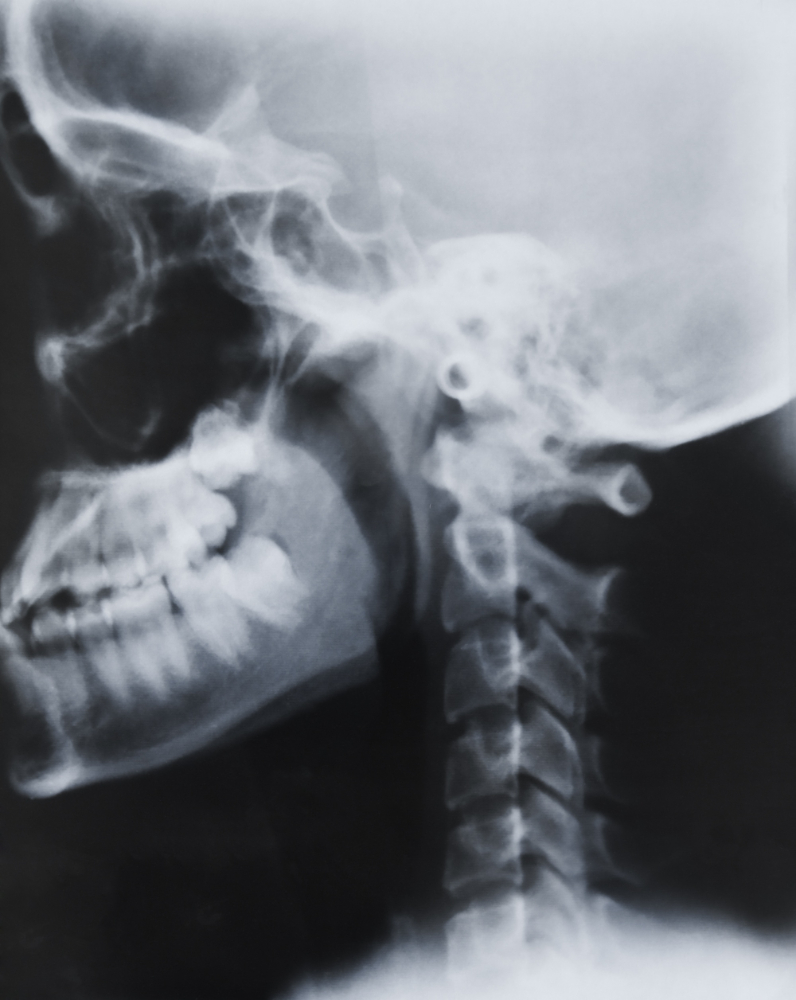

At Diagnopein in karad, we offer advanced imaging services including the X-Ray Left Mastoid Schüller’s View — a specialized diagnostic X-ray designed to assess the mastoid part of the temporal bone, middle ear, and related structures on the left side. This radiographic technique helps clinicians identify infections, bone erosions, and anatomical variations of the ear and skull base with high accuracy.

The Schüller’s View is a lateral oblique projection of the skull that focuses on visualizing the mastoid air cells, external auditory canal, and tympanic cavity. It remains one of the most reliable and widely used methods for mastoid evaluation.

This X-ray is crucial for evaluating chronic ear infections, mastoiditis, cholesteatoma, and post-surgical mastoid cavities. The Left Mastoid Schüller’s View allows radiologists to visualize the detailed anatomy of the temporal bone and its relationship to the middle and inner ear structures.